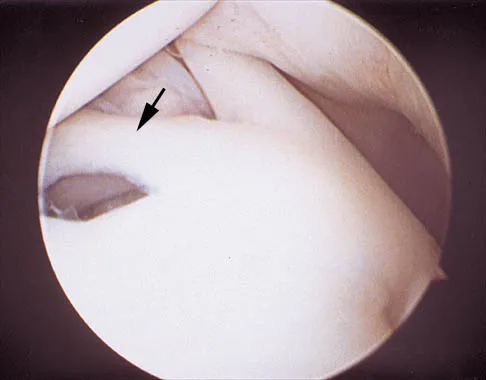

Question 99High Yield

A 24-year-old athlete has a painful right shoulder. Figure 30 shows an intra-articular photograph that was obtained through a posterior portal during arthroscopy; the labrum is indicated by the arrow. Based on these findings, management should consist of

Explanation